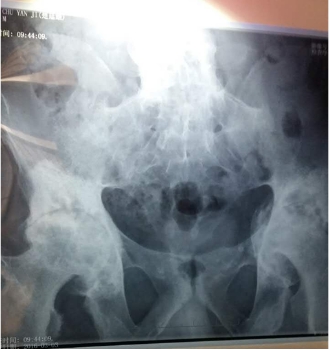

(图:患者提供的3月3日检查的片子)

[由片子可见,楚先生已经出现强直性脊柱炎合并股骨头坏死,股骨头表面粗糙、骶髂关节已经炎性融合,左侧关节间隙变窄、右侧关节间隙消失,活动受限严重。这也是患者无法弯腰、不能活动的主因。]

(图:患者提供的骶髂关节、股骨头部位片子)医学解读:患者强直导致周边骨质纤维化,股骨头出现局部塌陷,左侧塌陷严重,所以医生建议行关节置换手术,改善患者的活动功能。